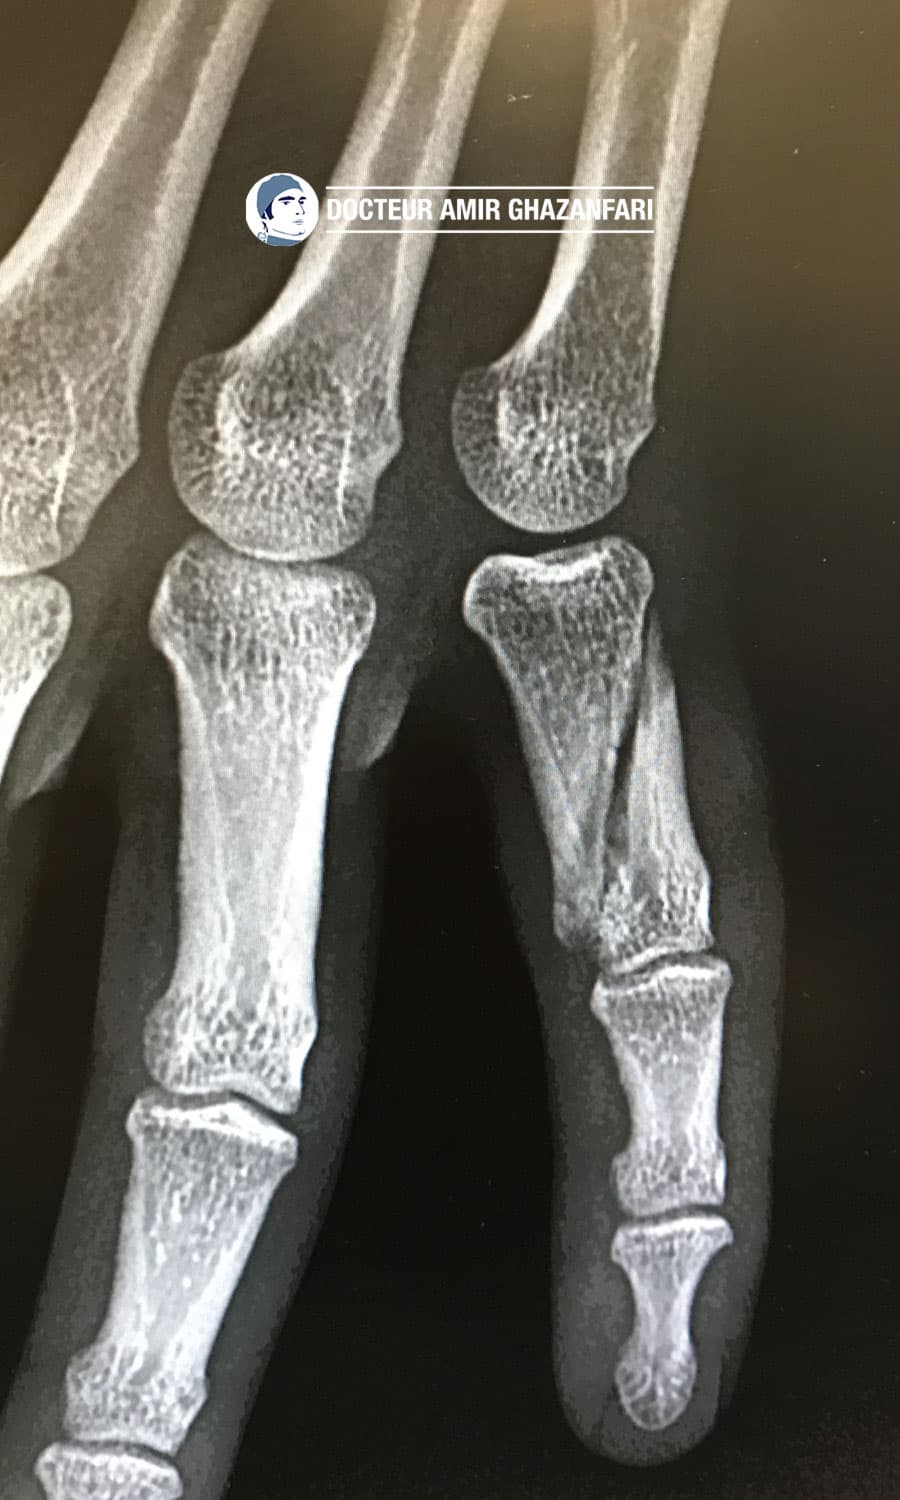

Fracture déplacée et instable de la première phalange de l'auriculaire traitée par un double vissage en compression